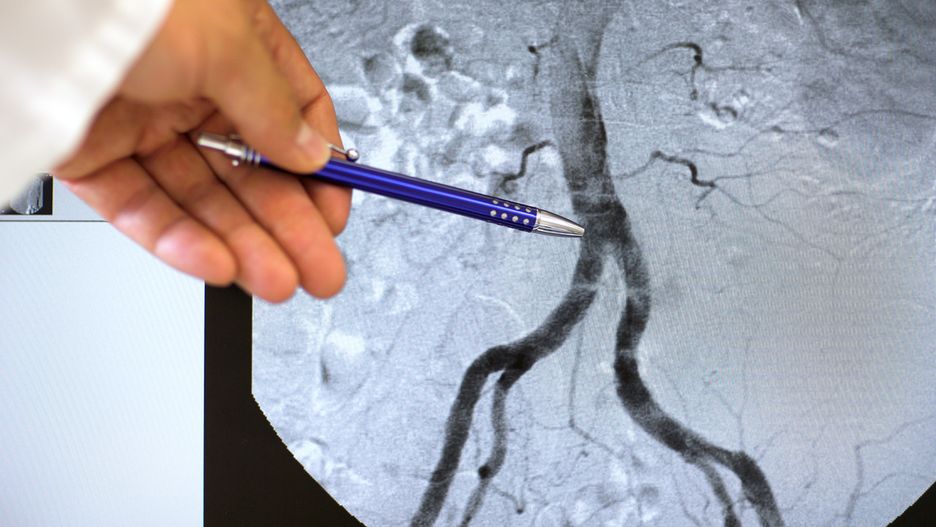

W nieinwazyjnej diagnostyce obrazowej istotną rolę odgrywają: echokardiografia przezklatkowa (TTE) i przezprzełykowa (TEE), tomografia komputerowa (CT) oraz rezonans magnetyczny (MR). Leczenie często jest operacyjne.

Przyjmuje się, że w okolicy serca aorta ma średnicę około 40 mm. Im dalej, tym jest mniejsza. Gdy obserwuje się jej poszerzenie o więcej niż 50 % w stosunku do prawidłowej szerokości, świadczy to o patologii, jaką jest tętniak aorty.

Najczęściej tętniak aorty pojawia się w odcinku brzusznym (tętniak aorty brzusznej), jednak może występować na każdym odcinku aorty (np. tętniak aorty piersiowej). Objawy ich obecności nie pojawiają się zawsze. To dlatego zwykle tętniaki są wykrywane przypadkowo.

Tętniak aorty, niezależnie od lokalizacji, stanowi zagrożenie dla zdrowia i życia. Największym niebezpieczeństwem jest ryzyko jego pęknięcia. Najskuteczniejszą metodą leczenia tętniaków aorty jest operacyjne usunięcie połączone z wszczepieniem protezy w miejscu usuniętego fragmentu naczynia. Im wcześniej zmiana zostanie wykryta, tym szybciej kardiolog podejmie odpowiednie działania.